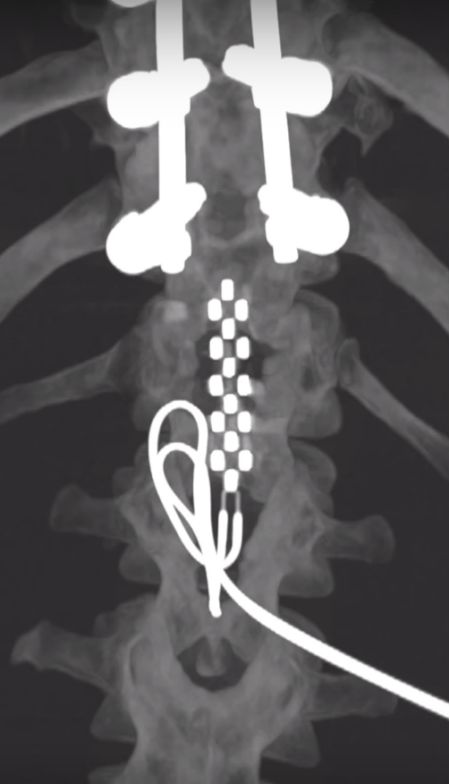

Jered Chinnock脊柱受伤术后X光(来源:梅奥诊所)

之后,研究团队对Jered Chinnock进行了手术,将电极阵列植入受伤部位下方、腰骶部脊髓背侧硬膜外表面,将脉冲发生器植入其右上腹的皮下,大小与心脏起搏器相当,电极阵列与脉冲发生器相连接。

在受伤处下方植入电极阵列(来源:梅奥诊所)